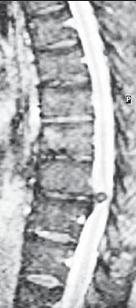

МРТ № 1

На магнитно-резонансной томографии (МРТ) № 1 — шейный отдел позвоночника, в относительно нормальном состоянии.

Шейный отдел позвоночника должен иметь нормально выраженный физиологический лордоз, не должно быть гиполордоза или гиперлордоза, а так же кифотических деформаций.

Ширина спинного мозга: сагиттально > 6–7 мм

1. Сагиттальный размер позвоночного канала на уровне:

СI 21 мм

СII 20 мм

СIII 17 мм

CIV-CVII = 14 мм

2. Высота межпозвонковых пространств:

СII < СIII < СIV < СV < СVII  СVII

3. Ширина спинномозгового канала: поперечный диаметр на уровне ножек: > 20–21 мм